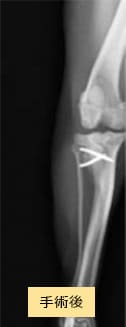

チワワ×マルチーズ(4歳10ヶ月齢、雌)グレードU〜V 外科手術

- 【初診時症状】

- 他院にて両後肢パテラグレードVと診断

手術を希望されて受診

- 【手術】

- 滑車溝形成術、脛骨粗面転位術、関節包縫縮を実施

- 【経過】

- 性格的にご自宅での安静が難しいため、術後2週間入院。術後4週間で屋内での運動制限を徐々に解除、8週間でお散歩の距離を少しずつ伸ばしていくも問題なし。

現在は制限なく生活